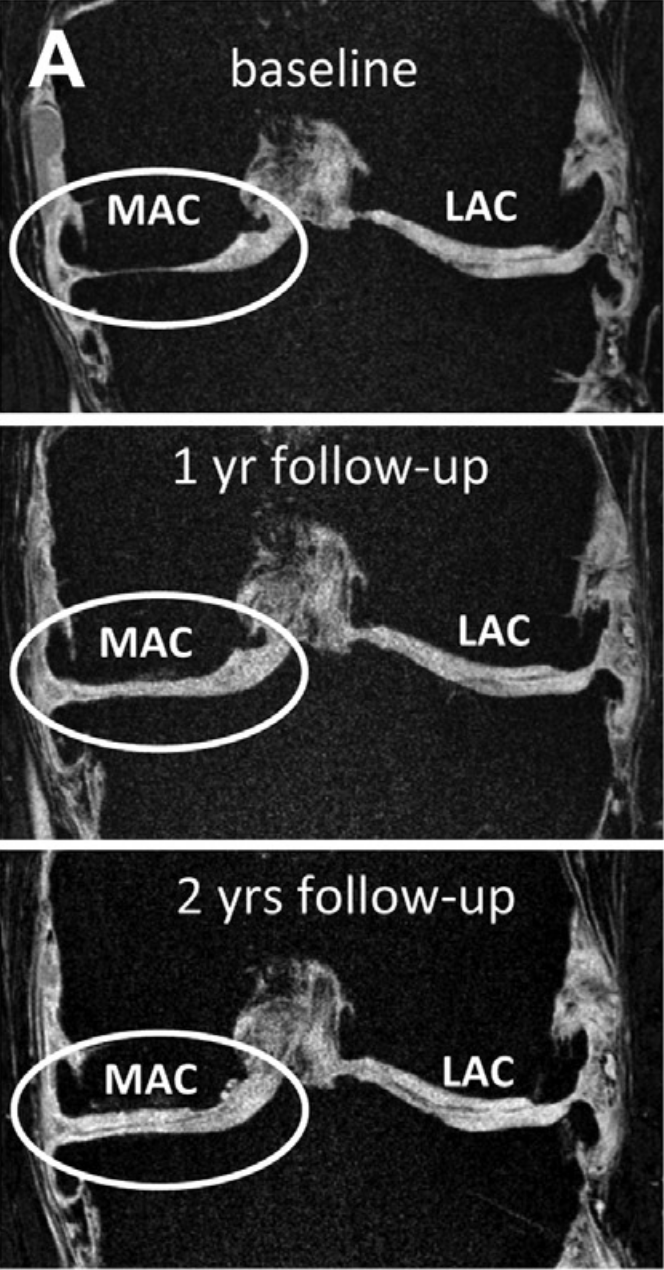

Diese niederländische Pilotstudie umfasste 20 Patienten mit fortgeschrittener

Kniearthrose (durchschnittlich 48 Jahre alt), die Kniegelenks-Ersatzoperationen

ablehnen wollten oder aufgrund ihres Alters nicht für eine Operation infrage kamen.

Die Patienten wurden mit kontinuierlicher Gelenkdistraktionstherapie behandelt,

bei der ein Fixateur Externe am Knie angebracht wurde, der die beiden Knochenseiten

über etwa 14 Tage hinweg mit circa 0,5 mm pro Tag auseinander zog. Anschließend

folgte eine Immobilisierungsphase. Nach einem Jahr zeigte sich radiographisch ein

signifikanter Anstieg des Gelenksspaltes von durchschnittlich 2,7 auf 3,6 mm.

MRT-Untersuchungen belegten einen echten Knorpelzuwachs von 2,4 auf 3,0 mm

sowie eine Reduktion entknorpelter Knochenflächen von 22 Prozent auf 5 Prozent

(p<0,001). Klinisch verbesserten sich die WOMAC-Schmerzwerte deutlich von

55 auf 23 Punkte, und 80 Prozent der Patienten zeigten eine Verbesserung von

mehr als 25 Prozent.

Zusammenfassung der Studie

Diese Folgestudie der niederländischen Forschergruppe verfolgte die ursprünglichen 20 Gelenkdistraktionspatienten über 2 Jahre nach ihrer Behandlung. Die Ergebnisse waren beeindruckend: Die klinische Verbesserung (Schmerz, Funktionalität) blieb vollständig erhalten – der WOMAC-Score war im Jahr 2 ähnlich niedrig wie nach 1 Jahr. Wichtiger noch: Die strukturellen Verbesserungen waren ebenfalls stabil oder verstärkt sich sogar. Die Knorpeldicke (gemessen durch MRT) stieg weiter an von 2,35 mm (Baseline) auf 2,78 mm nach 2 Jahren (p=0,03). Das Gelenkspaltminimum (JSW) – ein Marker unter Belastung – stieg von 1,1 mm auf 1,7 mm (p=0,03). Diese Zunahme unter Last-tragenden Bedingungen deutet darauf hin, dass der neue Knorpel mechanisch robust und belastbar ist, nicht einfach Ödem oder Bindegewebe. Biochemische Marker des Knorpelstoffwechsels zeigten weiterhin Zeichen von Reparatur, nicht Degeneration.

Bedeutung der Studie

Diese 2-Jahres-Langzeitstudie ist kritisch wichtig für die Validierung von Gelenkdistraktionstherapie als echte regenerative Behandlung – nicht nur eine vorübergehende Erleichterung. Die Besonderheit ist, dass nicht nur die Symptome besser werden, sondern die objektiven strukturellen Veränderungen (Knorpeldicke, Gelenkspalt) sich weiterhin verbessern über 2 Jahre. Dies spricht gegen die Hypothese, dass die anfängliche Verbesserung einfach auf Inflammation, Ödem oder andere vorübergehende Faktoren zurückzuführen ist. Vielmehr deutet es auf echte Knorpelregeneration hin. Die Tatsache, dass die neu gebildeten Gewebe unter mechanischer Last ihre Dicke und Funktion bewahren, ist besonders überzeugend. Diese Studie eröffnet auch langfristige Hoffnung für Patienten mit Endstadium-Arthrose: Statt automatische Knie-Prothesen, könnte eine biologische Reparatur möglich sein, die über Jahre erhalten bleibt. Dies hat auch wirtschaftliche Implikationen – Langzeitkosten könnten durch Vermeidung von Prothesen gesenkt werden. Die Studie hat 200+ Zitationen und inspirierte viele weitere prospektive Studien weltweit. Sie eröffnet auch neue Fragen: Was sind die Langzeit-Follow-up-Daten (5, 10 Jahre)? Können andere Gelenke (Hüfte, Sprunggelenk) auch von dieser Therapie profitieren? Können andere nicht-operative Techniken (Stammzell-Therapie, biologische Implantate) mit Gelenkdistraktionstherapie kombiniert werden?